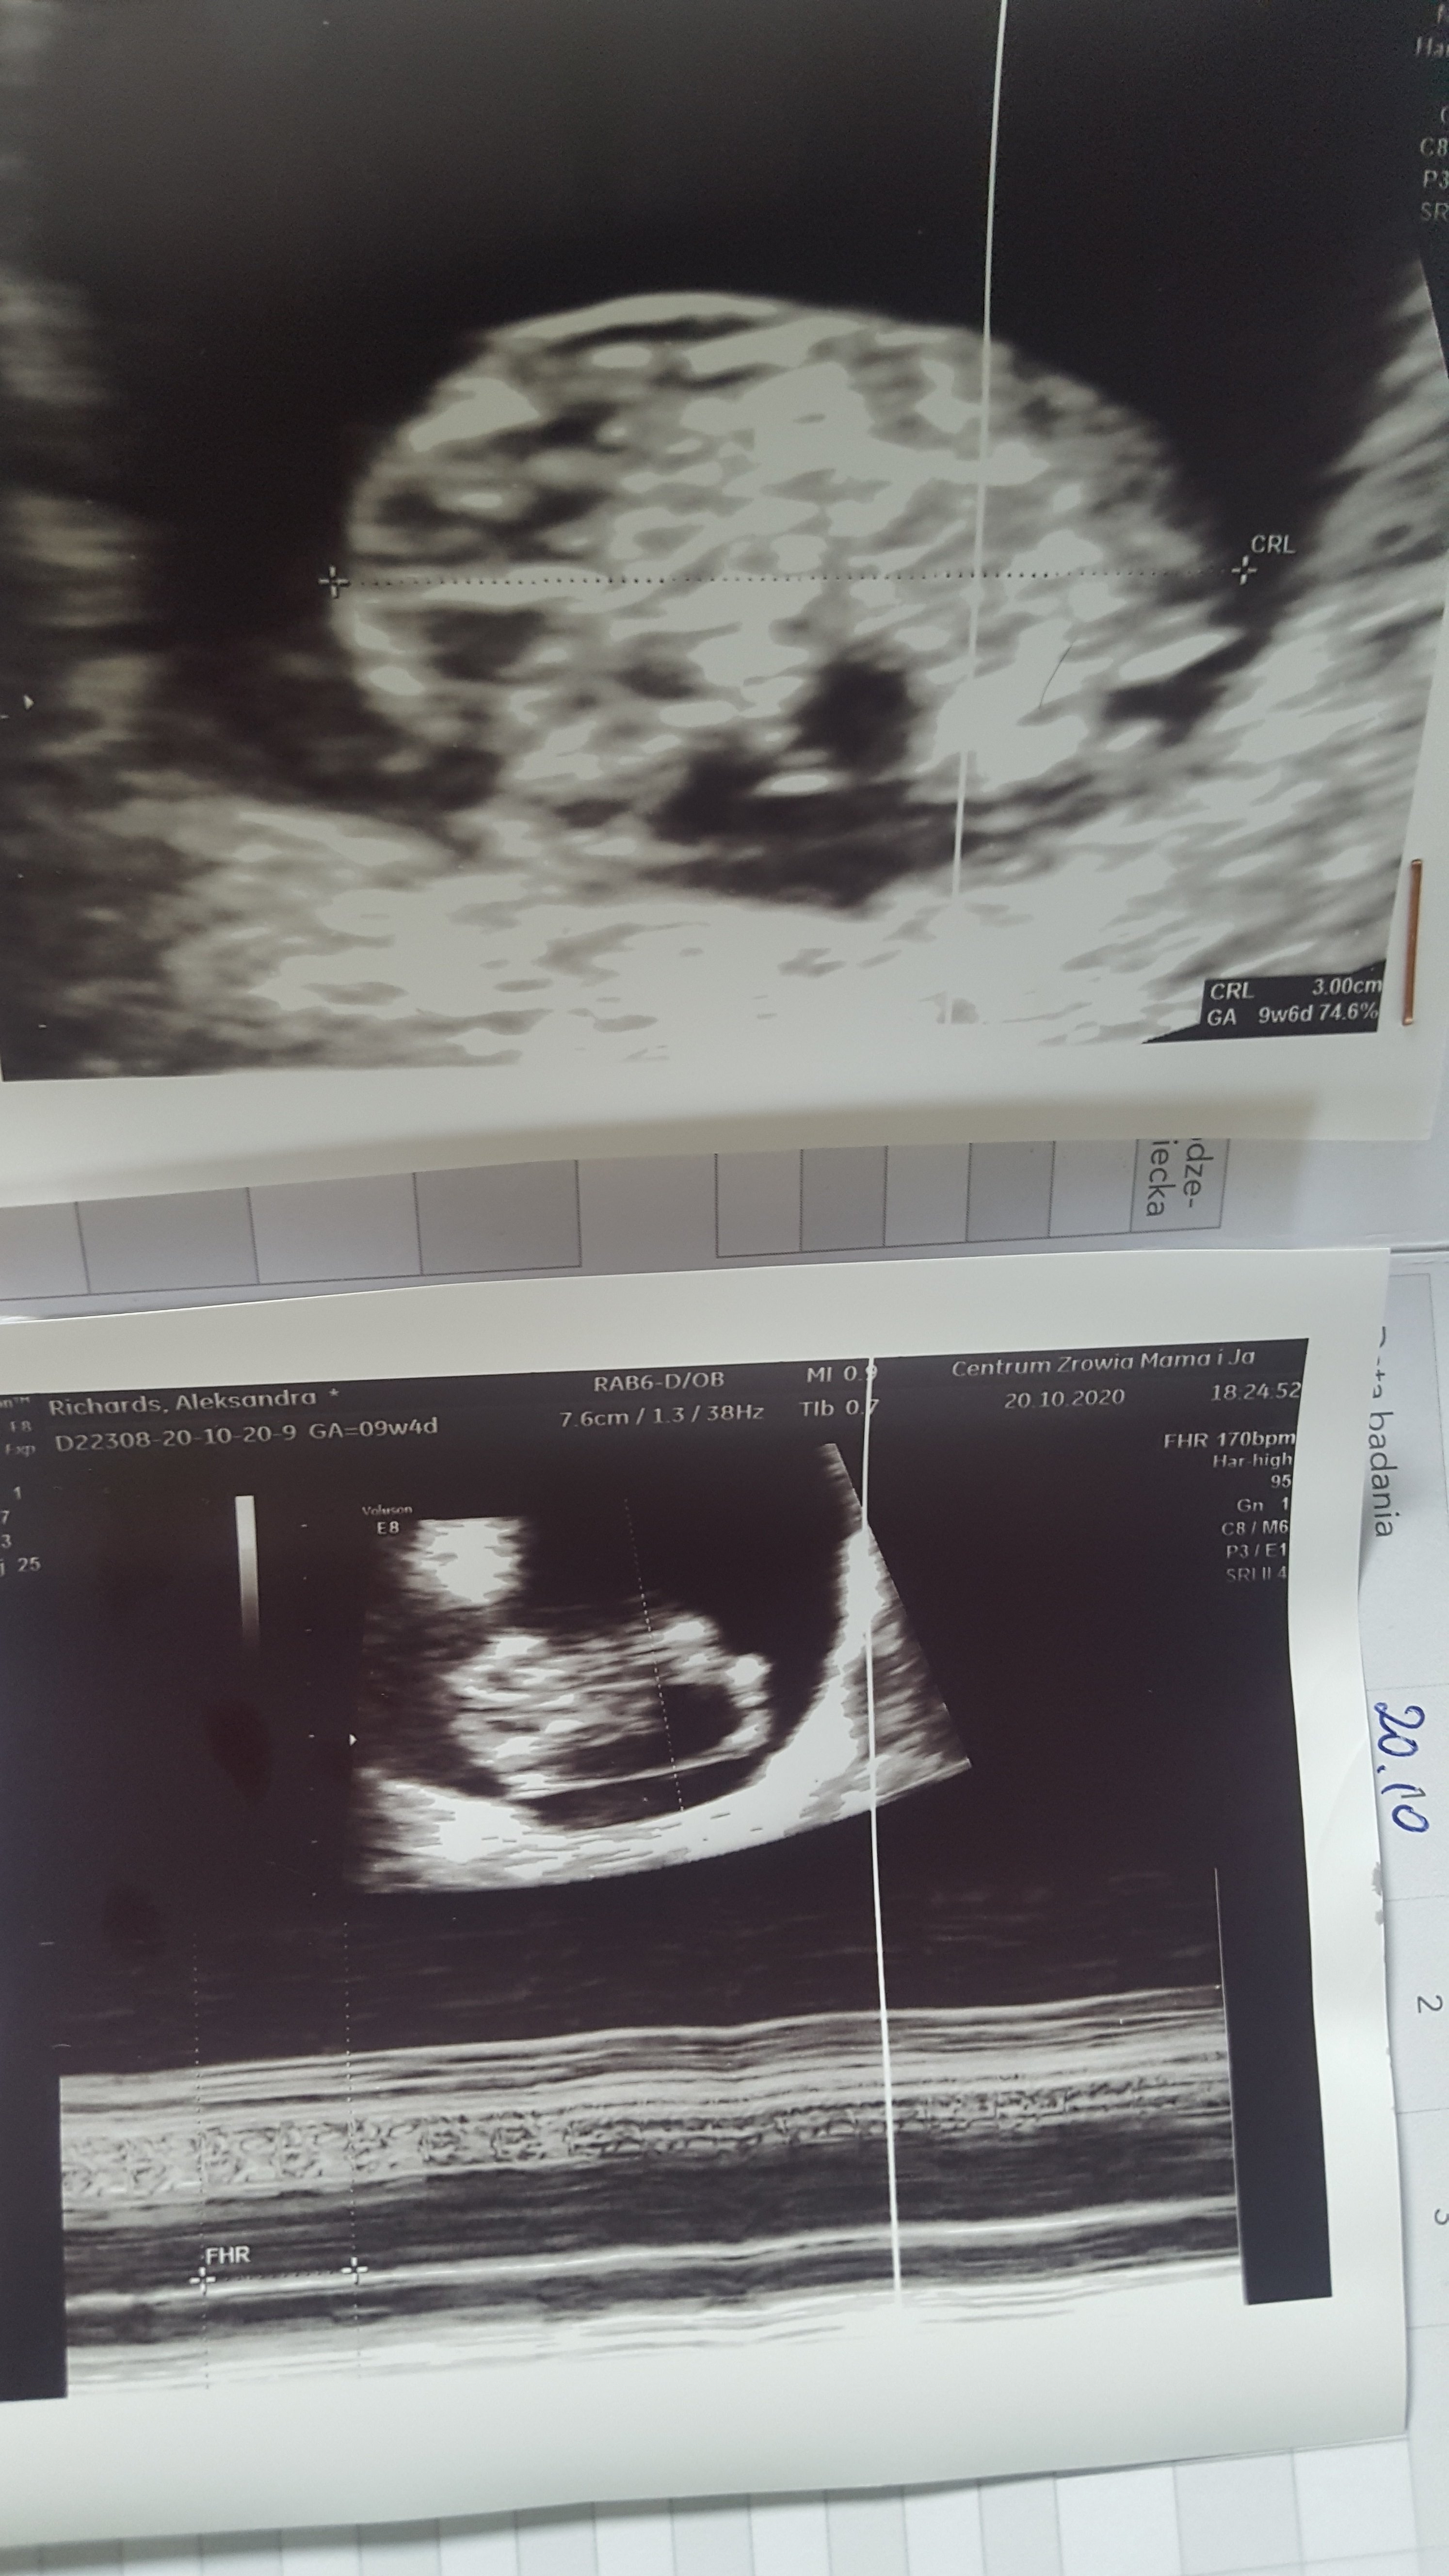

Nie odzywałam sie ponad tydzien poniewaz mdłości I super zmeczenie poprostu mnie wykańcza. Ale jest ok.... co ja mowie jest cudownie. Dzidzia ma juz 3cm I serducho bije 170

Prenatalne mam 5.11 w moje 39te urodzinki.

Załączniki

• 20201021_112304.jpg

20201021_112304.jpg

1,3 MB · Wyświetleń: 106